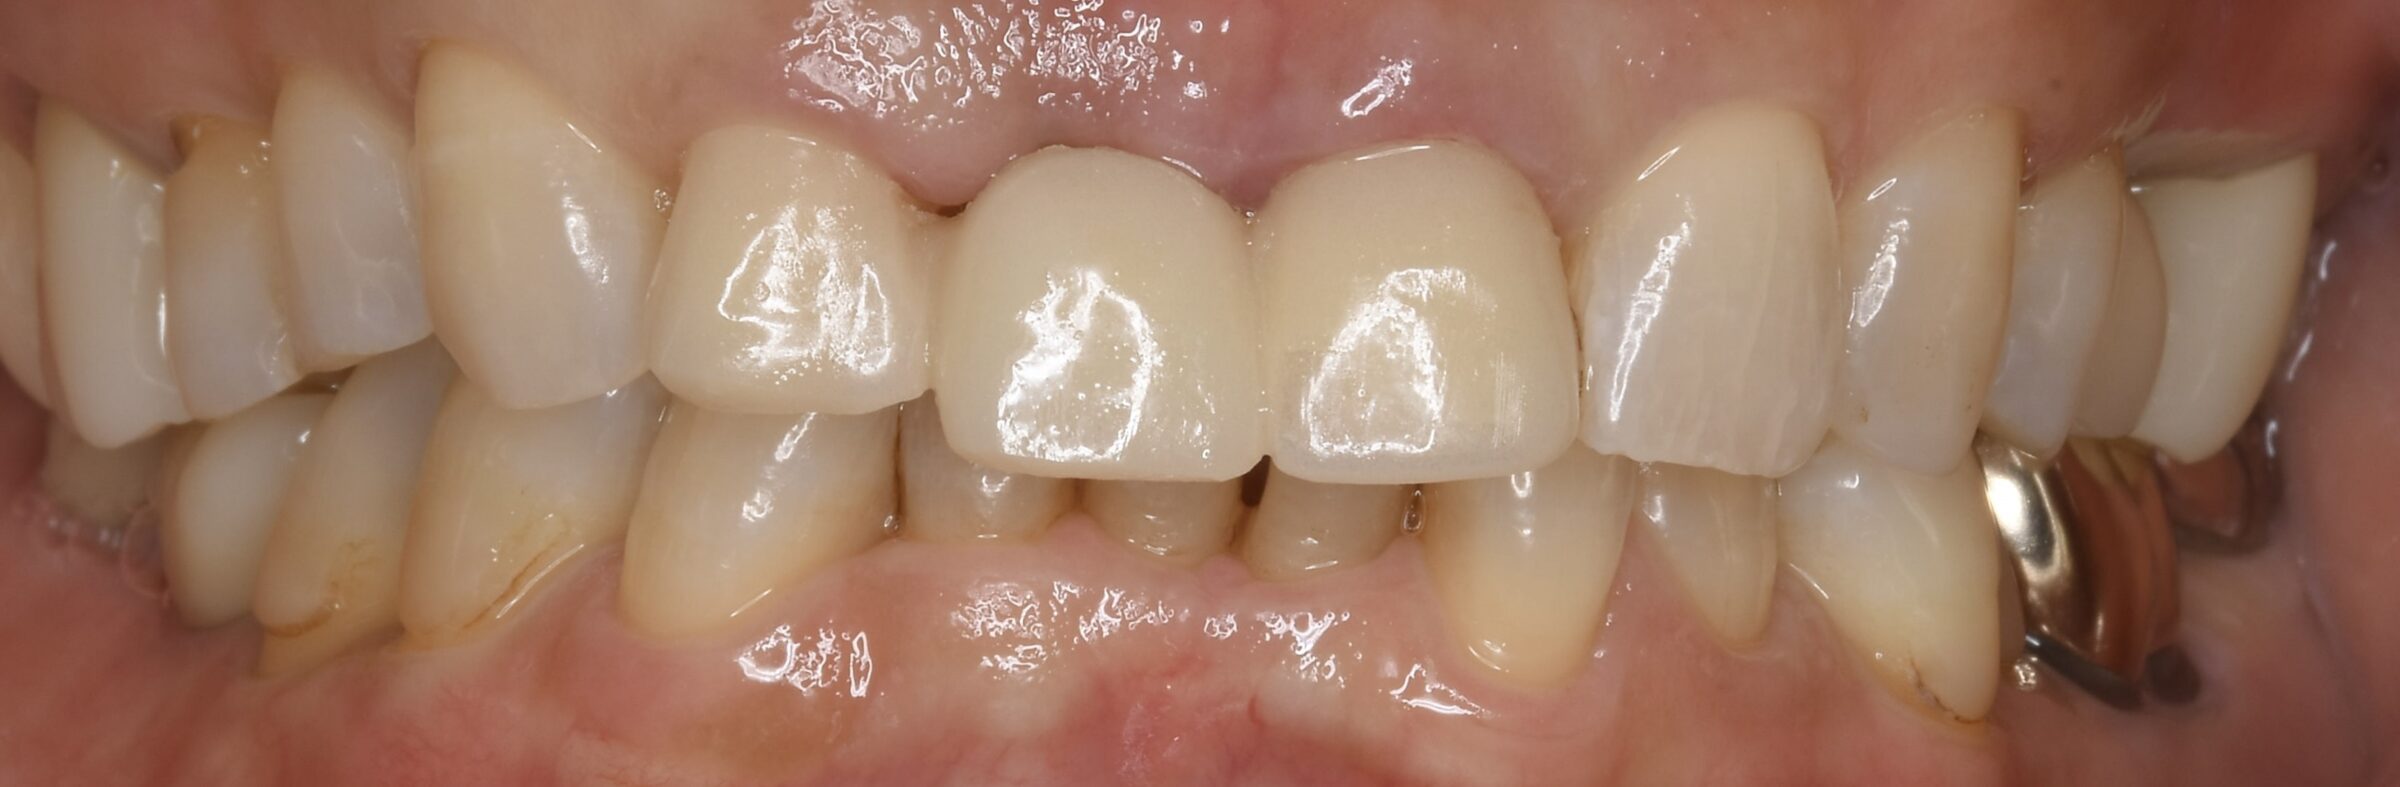

治療後の口腔内写真

たった3本の治療でも、ここまで口元の印象が改善できます。